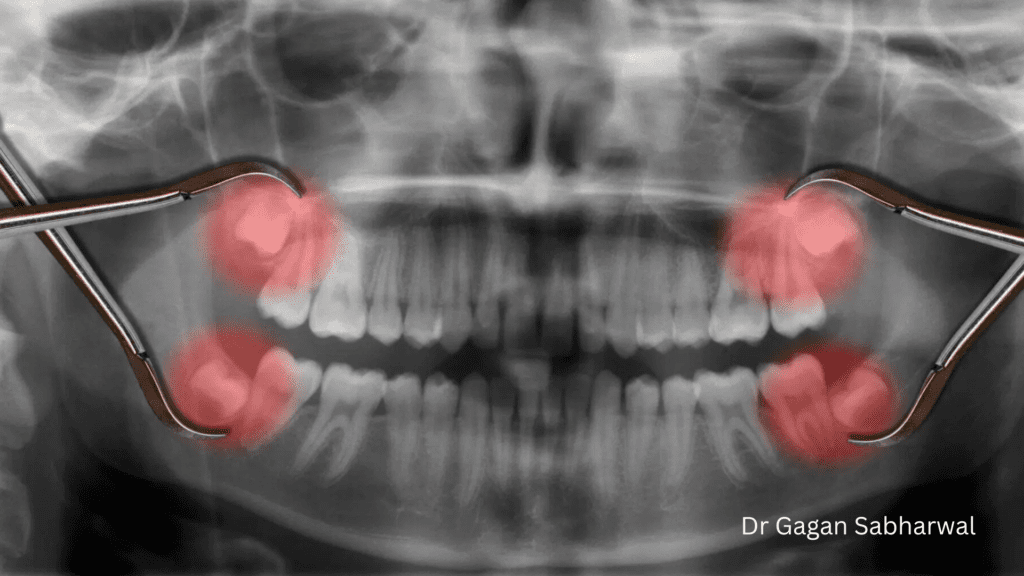

Wisdom Tooth Surgery Dubai

Wisdom tooth extraction is a routine procedure, but recovery plays an essential role in healing. Knowing what to expect can help reduce anxiety and improve outcomes.